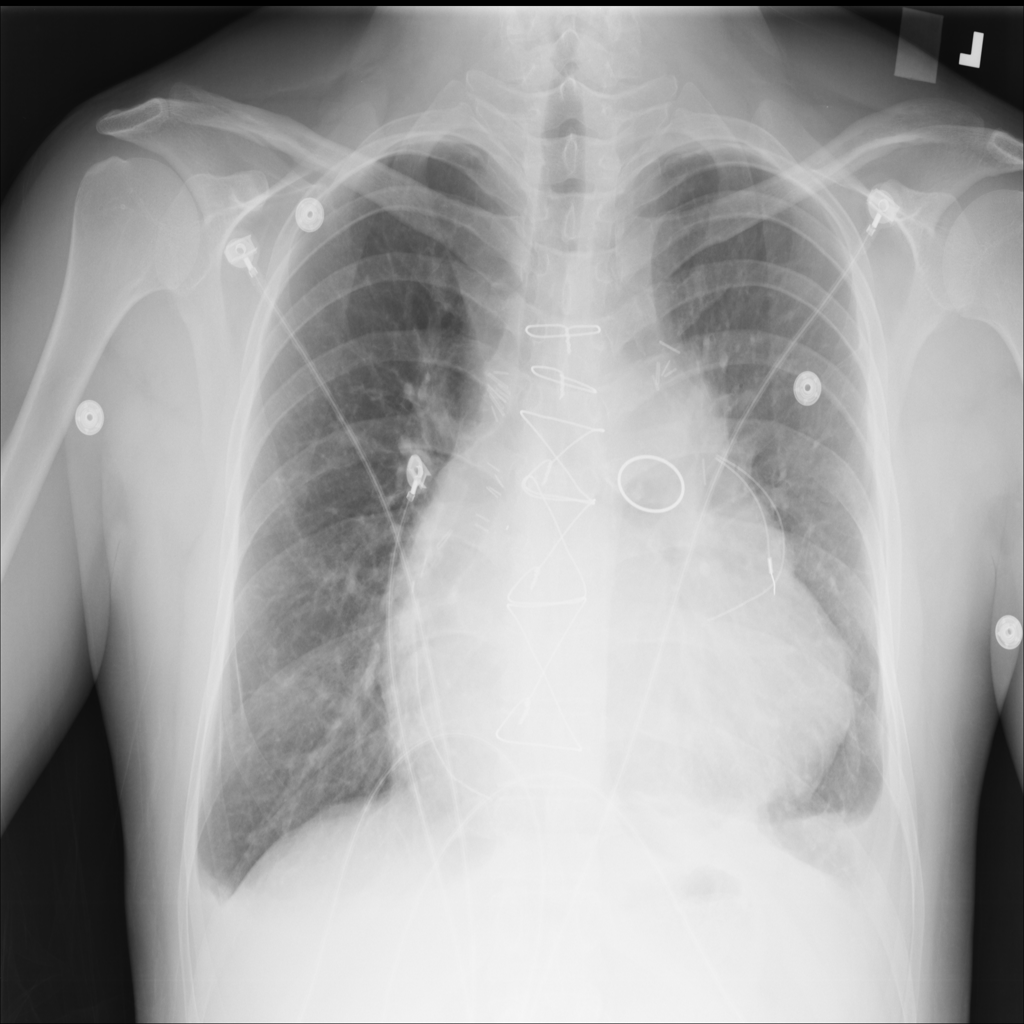

PAT-E81B · IMG-000Effusion

PAT-E81B · IMG-000

PA